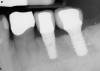

Figure 17  In another case, the mandibular left second molar was fractured and hopeless.

Figure 17

Figure 18  Following hemisection and extraction of the hopeless molar, implants were placed in the first and second molar positions, utilizing specific interradicular bone preparation techniques. Note the positioning of the implant in the second molar site so as to provide adequate dimension for ideal placement of an implant in the first molar area.

Figure 18

Figure 19  A radiograph taken after 46 months in function demonstrates the stability of the crestal peri-implant bone around both implants.

Figure 19

Case reports of these techniques can be seen in Figure 11 through Figure 19.